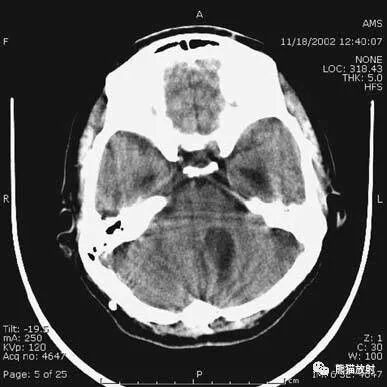

动脉瘤破裂导致蛛网膜下腔出血、

脑室积血、非交通性脑积水。

与外伤性蛛网膜下腔出血不同,动脉瘤破裂导致的SAH常不累及大脑凸面,而位于基底池附近。脑动脉瘤常位于鞍上池的Willis环血管。

A:四脑室积血;

B:中脑导水管、环池、右侧侧脑室颞角积血,前交通动脉处(动脉瘤好发位置)出血密度较高;

C:三脑室积血;